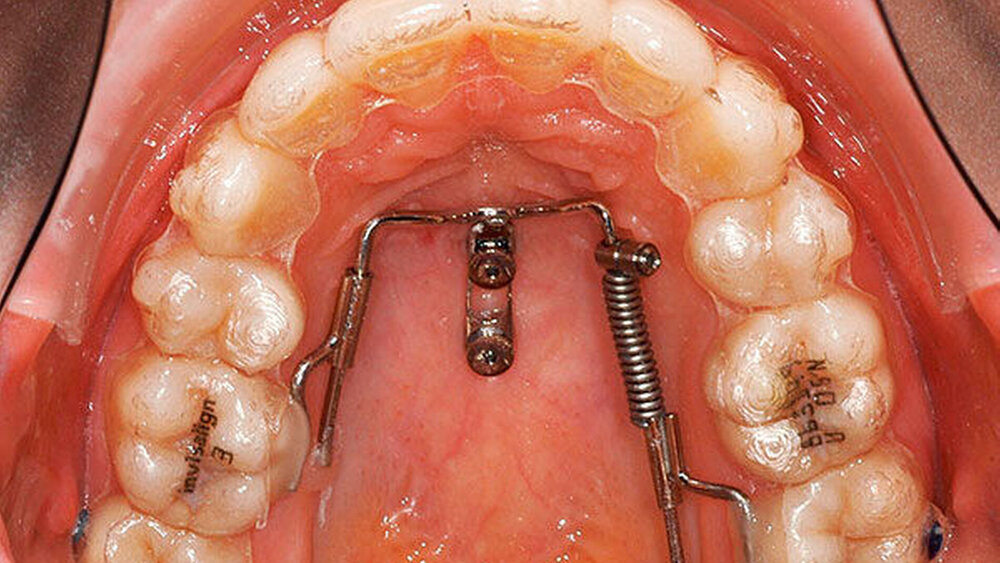

Die geeignete Insertionsstelle hat eine dünne Weichgewebsschicht (circa 1 mm) und liegt posterior der Gaumenfalten (T-Tone [Wilmes, 2016]). Als Vorteil müssen hier die gute Knochenqualität ohne Risiko der Zahnverletzung, gepaart mit der befestigten Schleimhaut genannt werden. Um das Risiko einer Implantat-Kippung beziehungsweise eines Verlusts weiter zu verringern, kann eine Verblockung von zwei Mini-Implantaten erfolgen [Wilmes, 2008a]. Eine sichere Kopplung vom Mini-Implantat zur kieferorthopädischen Apparatur kann erreicht werden, wenn Abutments (Stahlkappen) fest auf ein Mini-Implantat aufgeschraubt werden können. Der Beneslider (Abbildung 1) [Wilmes, 2008b; Wilmes, 2010; Wilmes, 2009] hat sich als Distalisierungs-Apparatur mittlerweile sehr bewährt [Nienkemper, 2014].

Möglich ist sowohl das zweizeitige Vorgehen (erst Distalisierung mit Slider, dann Finishing mit Alignern) als auch das simultane Vorgehen (gleichzeitig Distalisierung der Molaren und Nivellierung der Frontzähne). Um das gleichzeitige Verwenden von Alignern und Slidern zu ermöglichen, wird als Alternative zu einem Molarenband ein Tube (Abbildung 1b) an die Palatinalfläche geklebt (Abbildungen 1c und 1d). Die Aligner können an dieser Kopplungsstelle von Zahn und Slider ausgeschnitten sein oder diese Kopplungsstelle bedecken, ähnlich einem Attachment.

Die Behandlung begann mit Scans für die Aligner-Schienen (Invisalign). Die Schienen wurden mit sogenannten „button cut outs“ bestellt, damit die Kopplungsstellen für den Slider frei bleiben konnten (Abbildung 1d). Nach Eintreffen der Schienen wurden die beiden Mini-Implantate (Abbildung 11) und der Slider (Abbildung 12) eingesetzt. Ziel war die einseitige Distalisierung im zweiten Quadranten um circa 4 bis 5 mm, um die Frontmitte im Oberkiefer korrigieren zu können. Nach sieben Monaten waren viele kleine Lücken im zweiten Quadranten erkennbar (Abbildung 13). Nach zehn Monaten war der zweite obere linke Molar in eine Klasse-I-Verzahnung bewegt worden (Abbildung 14), man erkennt eine körperliche Distalisierung ohne Kippung (Abbildung 14). Auch hier wurde der Slider anschließend mit einer Drahtligatur von einem aktiven Distalisierungsgerät in ein passives Molarenverankerungsgerät modifiziert (Abbildung 15, nach 14 Monaten). Nach 17 Monaten waren die Lücken fast komplett nach distal geschlossen, so dass die Korrektur der Oberkiefer-Frontmittenverschiebung sowie der Frontprotrusion weiter erfolgen konnte (Abbildung 16). Die Therapie wurde nach einer Behandlungsdauer von 22 Monaten erfolgreich beendet (Abbildungen 17 und 18). Nach einer Retentionszeit von einem Jahr zeigte sich ein stabiles Ergebnis (Abbildung 19).